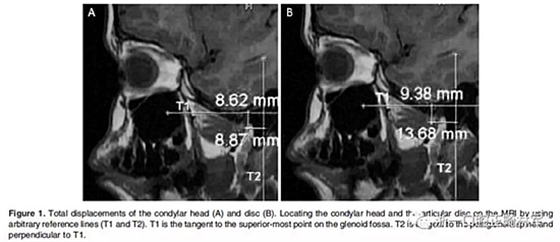

在生理休息位和另外三個位置獲得了四個咬合蠟型,這三個位置是水平前伸0mm時的HA1,水平前伸5mm時的HA2以及水平前伸7.5mm時的HA3。所有三個位置均保持垂直高度為5mm。病人分別將四個蠟型咬在嘴里,接受了5次連續(xù)磁共振掃描。外部標(biāo)記的Frankfort水平面保持垂直于掃描臺。標(biāo)記髁突頭和關(guān)節(jié)盤的位置,并在整個研究過程中對它們的位置變化進(jìn)行描繪(Figure 1和2;1Table 1和2)。